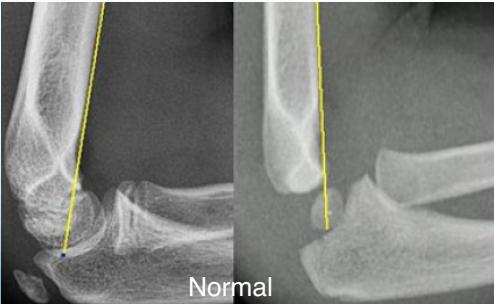

Anterior Humeral Line:

- A line drawn on a lateral view along the anterior surface of the humerus should pass through the middle third of the capitellum

Normal

Abnormal - Displaced posteriorly